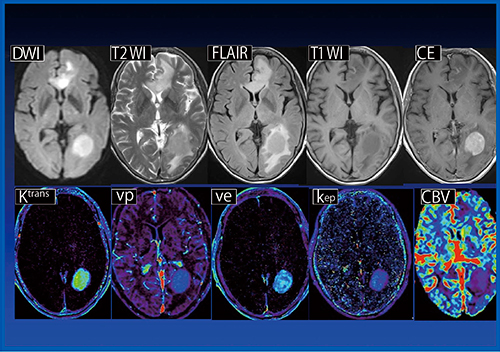

症例4(図4)は,glioblastoma(グレード4)である。非常に高い造影効果が認められ,Ktransは一部軽度高値,壊死部は低値であり,veはきわめて高値である。

図4 症例4:glioblastoma(グレード4)(80歳代,女性)